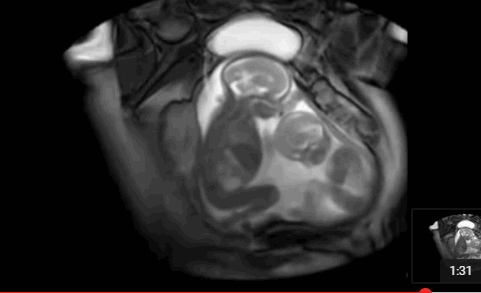

擁有雙胞胎寶寶父母當然都很幸福,雖然養育兒女付出了雙份的辛苦,但同時也收穫了雙份的歡樂。  他們在媽媽肚子的時候就已經頻頻互動,有時候還會親吻,打架!超級萌,超級感人!

雙胞胎居然在打架   其實雙胞胎是心有靈犀的,看下面的這兩對雙胞胎,你就知道有多羨慕了 1、當這對雙胞胎從媽媽肚子裡生出來的那一刻,竟讓醫院所有人都震驚了!!原來這對雙胞胎竟是.手拉手出生的! 而當寶寶生下來的一刻,大家都驚呆了  爸爸都感動的哭啦 2、雙胞胎中的弟弟出生就沒呼吸,哥哥給他加油打氣,居然拉起弟弟的手 出生時,弟弟被查出了胸部感染,需要靜脈注射抗生素,這時哥哥竟然把手伸過來緊緊握住了弟弟的手。 「不要怕,哥哥保護你。」  就在護士向媽媽解釋如何治療的時候,突然哥哥伸出手去摸瓊斯,弟弟感覺到了就伸手來回應,然後他倆的手緊緊的握在了一起。這一幕太令人難以置信了!